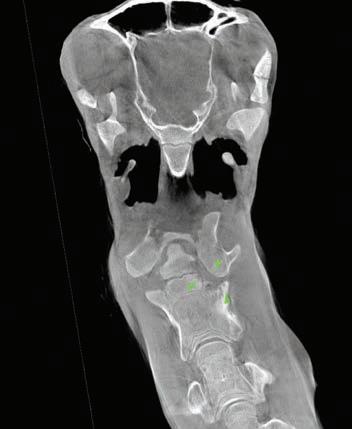

(Top) A three-dimensional reconstruction of an equine carpus (knee) from CT scan data generated by the imaging system. (Bottom) A CT scan of a foal neck with atlanto-axial joint sepsis and associated osteomyelitis of the axis (C2).